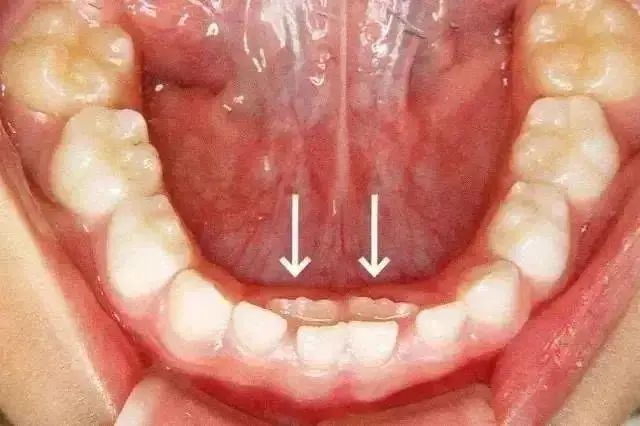

乳牙滞留是(shì)指恒牙相(xiàng)繼長(ch♥↔áng)出,乳牙未能(néng)及時(shí)脫落。或者恒牙未萌出,保留在恒牙列中<£✘。乳牙的(de)脫落與恒牙的(de)生(shēng)長(cháng)之間∑±→₽(jiān)存在著(zhe)密切的(de)關系。這(zhè)<± 種情況多(duō)見(jiàn)于換牙期的(de)下(xià)颌門(mén)牙,Ω♠÷©恒牙長(cháng)在舌側,乳牙留于唇側,出現(xiàn)雙排牙。

雙排牙一(yī)定要(yào)拔嗎(ma)?

很(hěn)多(duō)家(jiā)長(chδ áng)看(kàn)到(dào)孩子(zǐ)“雙排牙”後非常著(zhe)急,要(yào)求醫(yī→€✘)生(shēng)趕緊拔掉,這(zhè)樣對(duì)嗎(ma)?

過早過多(duō)的(de)拔牙,容易造成孩子(zǐ)牙颌畸形,←©φ拔不(bù)拔牙首先要(yào)看(kàn≥'β )恒牙萌出的(de)高(gāo)度,當恒牙隻萌出 1/3 或者 §↑♠±2/3 ,且前排牙齒還(hái)沒有(yǒu)松動的(de)情況下(xià),建議(yì)家(j"©iā)長(cháng)先讓孩子(zǐ)多(duō)吃(chī)硬性食物↕±(wù),比如(rú)啃蘋果、玉米等,促進自(zì)然脫落。